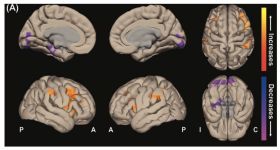

原發(fā)性進(jìn)行性失語(yǔ)癥(nfvPPA)的非流利/語(yǔ)法缺失性的亞表型表現(xiàn)為語(yǔ)法和運(yùn)動(dòng)語(yǔ)言的逐漸下降,這是由于大腦語(yǔ)言...